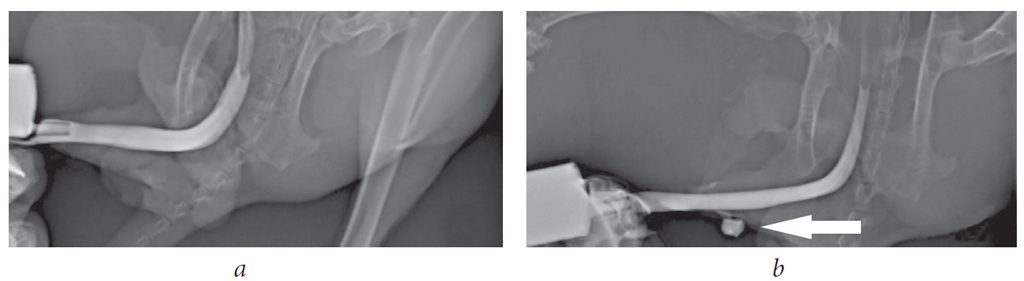

Для оценки состояния уретры в послеоперационном периоде всем кроликам после аутопсии была выполнена ретроградная уретрография (рис. 6). У животных всех трех групп проходимость уретры была сохранена.

Рис. 6. Ретроградные уретрограммы: а — просвет уретры сохранен; b — экстравазация контрастного вещества за пределы просвета уретры

Fig. 6. Retrograde urethrograms: a – the lumen of the urethra is preserved; b – the extravasation of the contrast agent outside the lumen of the urethra

На рис. 6 продемонстрирована полная проходимость уретры, сужений и дивертикулов не выявлено. У двух кроликов, которым ранее был диагностирован уретро-кожный свищ (группа 2), визуализировалась экстравазация контрастного вещества за пределы просвета уретры (рис. 6, b).

Таким образом, независимо от типа имплантированного для заместительной уретропластики материала, один из самых важных показателей — просвет уретры — был сохранен.